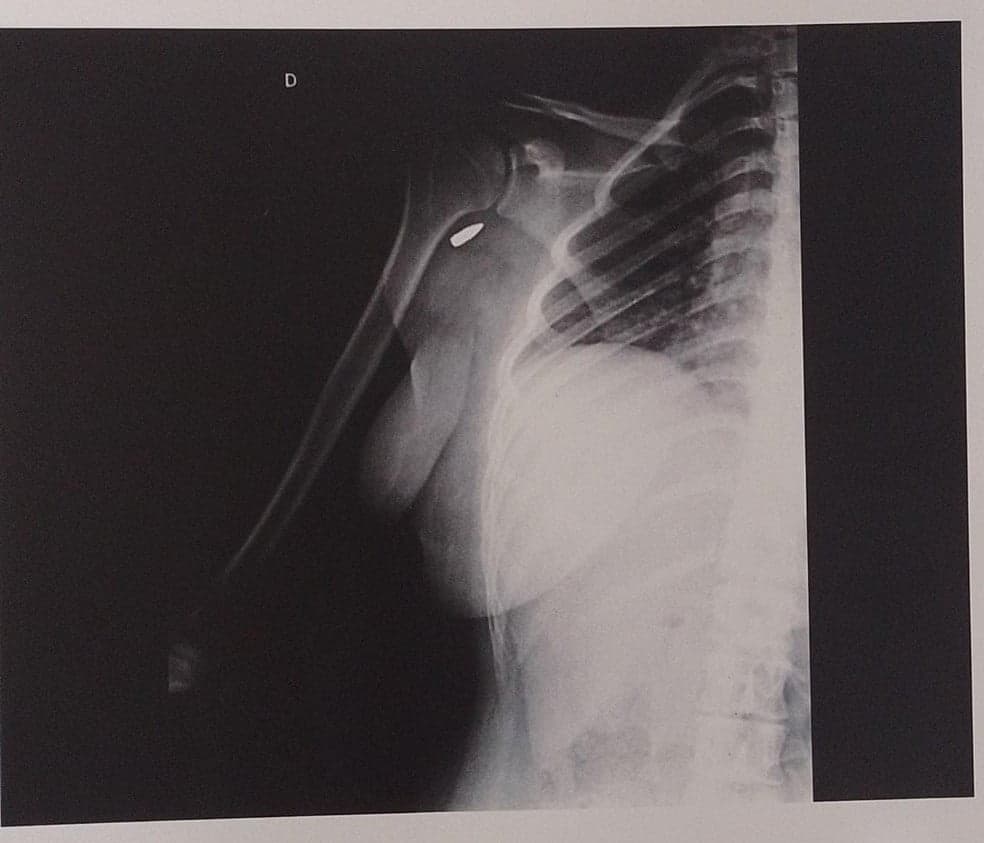

Raio-X de Renata comprovando o projétil em seu braço.

Ela continuou na festa. Mas então começou a sentir dores fortes e a não conseguir mais mexer o braço e a mão direitos. Renata e sua mãe foram a uma emergência e ao fazer um raio-X, os médicos descobriram a bala alojada no ombro dela.

A jovem segue com o projétil no ombro. “Eles [os médicos] falaram para mim que tentar tirar em uma cirurgia seria mais arriscado do que deixar [no braço] porque ficou muito perto de um nervo. Todos os médicos e funcionários do hospital falaram que eu tive muita sorte. Porque se ela entrasse mais um pouquinho ela tinha pegado no nervo e eu tinha perdido os movimentos”. A família da estudante só conseguiu marcar consulta com especialista para junho. Enquanto isso, buscam mais opiniões médicas sobre o que fazer com o caso.